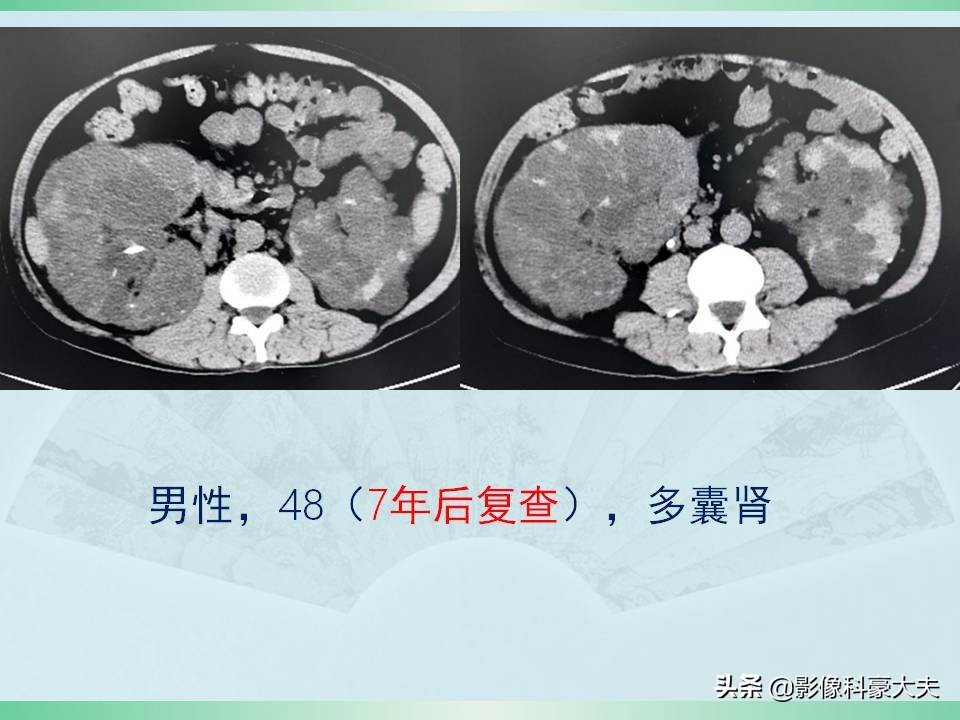

这是上面那位41岁男病人,没有做积极的对症治疗,7年后进展了,肝脏的多发囊肿也增多增大: